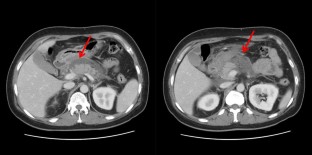

Fig. 1